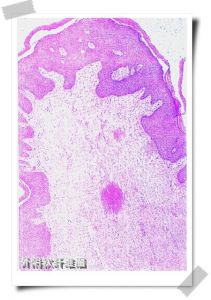

三、組織病理檢查:鏡下:可見在外陰生髮上皮有明顯的纖維血管間質的成分,表面覆以較為正常的或萎縮的鱗狀上皮,也可出現乳頭狀增生和過度角化。不同的病例,間葉成分可有很大的差別,有的細胞成分稀少,在疏鬆黏液水腫樣的間質中散布形態溫和的梭形的細胞。有的病例富有細胞,與表皮間沒有分界帶,細胞多形性明顯,有大量奇異大細胞及多核細胞,而且可有明顯增多的核分裂象。

四、免疫檢驗:免疫組化染色desmin、vimentin陽性,actin部分陽性,ER和PR間質細胞可陽性。